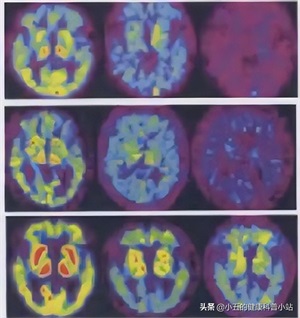

医生通过检查颅脑磁共振和血管造影后,诊断孙奶奶是患上了血管性痴呆,并且给孙奶奶开具了几种药物,其中一种药物叫奥拉西坦

奥拉西坦进入人体后可以选择性地作用于大脑皮层进行结合,并且可以具有选择性激活、保护大脑组织,促进受损神经细胞功能恢复,从而可以改善和整合大脑功能,如记忆力、学习能力、认知能力等

1、促进脑细胞的能量代谢

药理学研究表明奥拉西坦可以促进大脑皮层中乙酰胆碱的转运,增加大脑细胞对与胆碱摄取的亲和力,提高脑磷酸酯酶A1的活性,同时可以抑制脑磷脂分解,从

而有效激活酰苷酸激活酶,提高大脑中三磷酸腺苷(ATP)的合成,增加脑内能量储存,有效阴改善缺血、缺氧所造成的能量代谢不足,促进大脑细胞的能量代谢